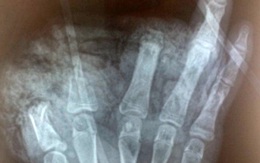

Thiếu niên 14 tuổi bị cụt 3 ngón bàn tay trái do nổ pin quạt tích điện

Ngày 23/10, Bệnh viện Hữu nghị Việt Đức cho biết vừa tiếp nhận em N.H.A.T (Nam, 14 tuổi), sống tại Trang Hạ, Thị xã Từ Sơn, Bắc Ninh bị cụt 3 ngón bàn tay trái do nổ pin của quạt tích điện.